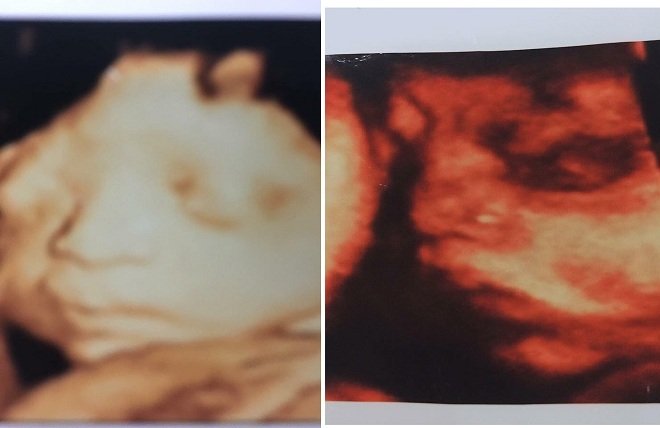

Chia sẻ về việc con dâu mang bầu, bà M. cho hay, con dâu bà mang thai đôi, vừa mới nghỉ để chờ sinh, dự tính đến ngày 25 -27/6 sẽ sinh mổ.

Tuy nhiên, các cháu bà chưa kịp chào đời, con dâu thông báo thai nhi bị chết lưu khiến gia đình ngỡ ngàng. Đáng nói, gia đình bà cũng thắc mắc không rõ thai nhi kia đang ở đâu.